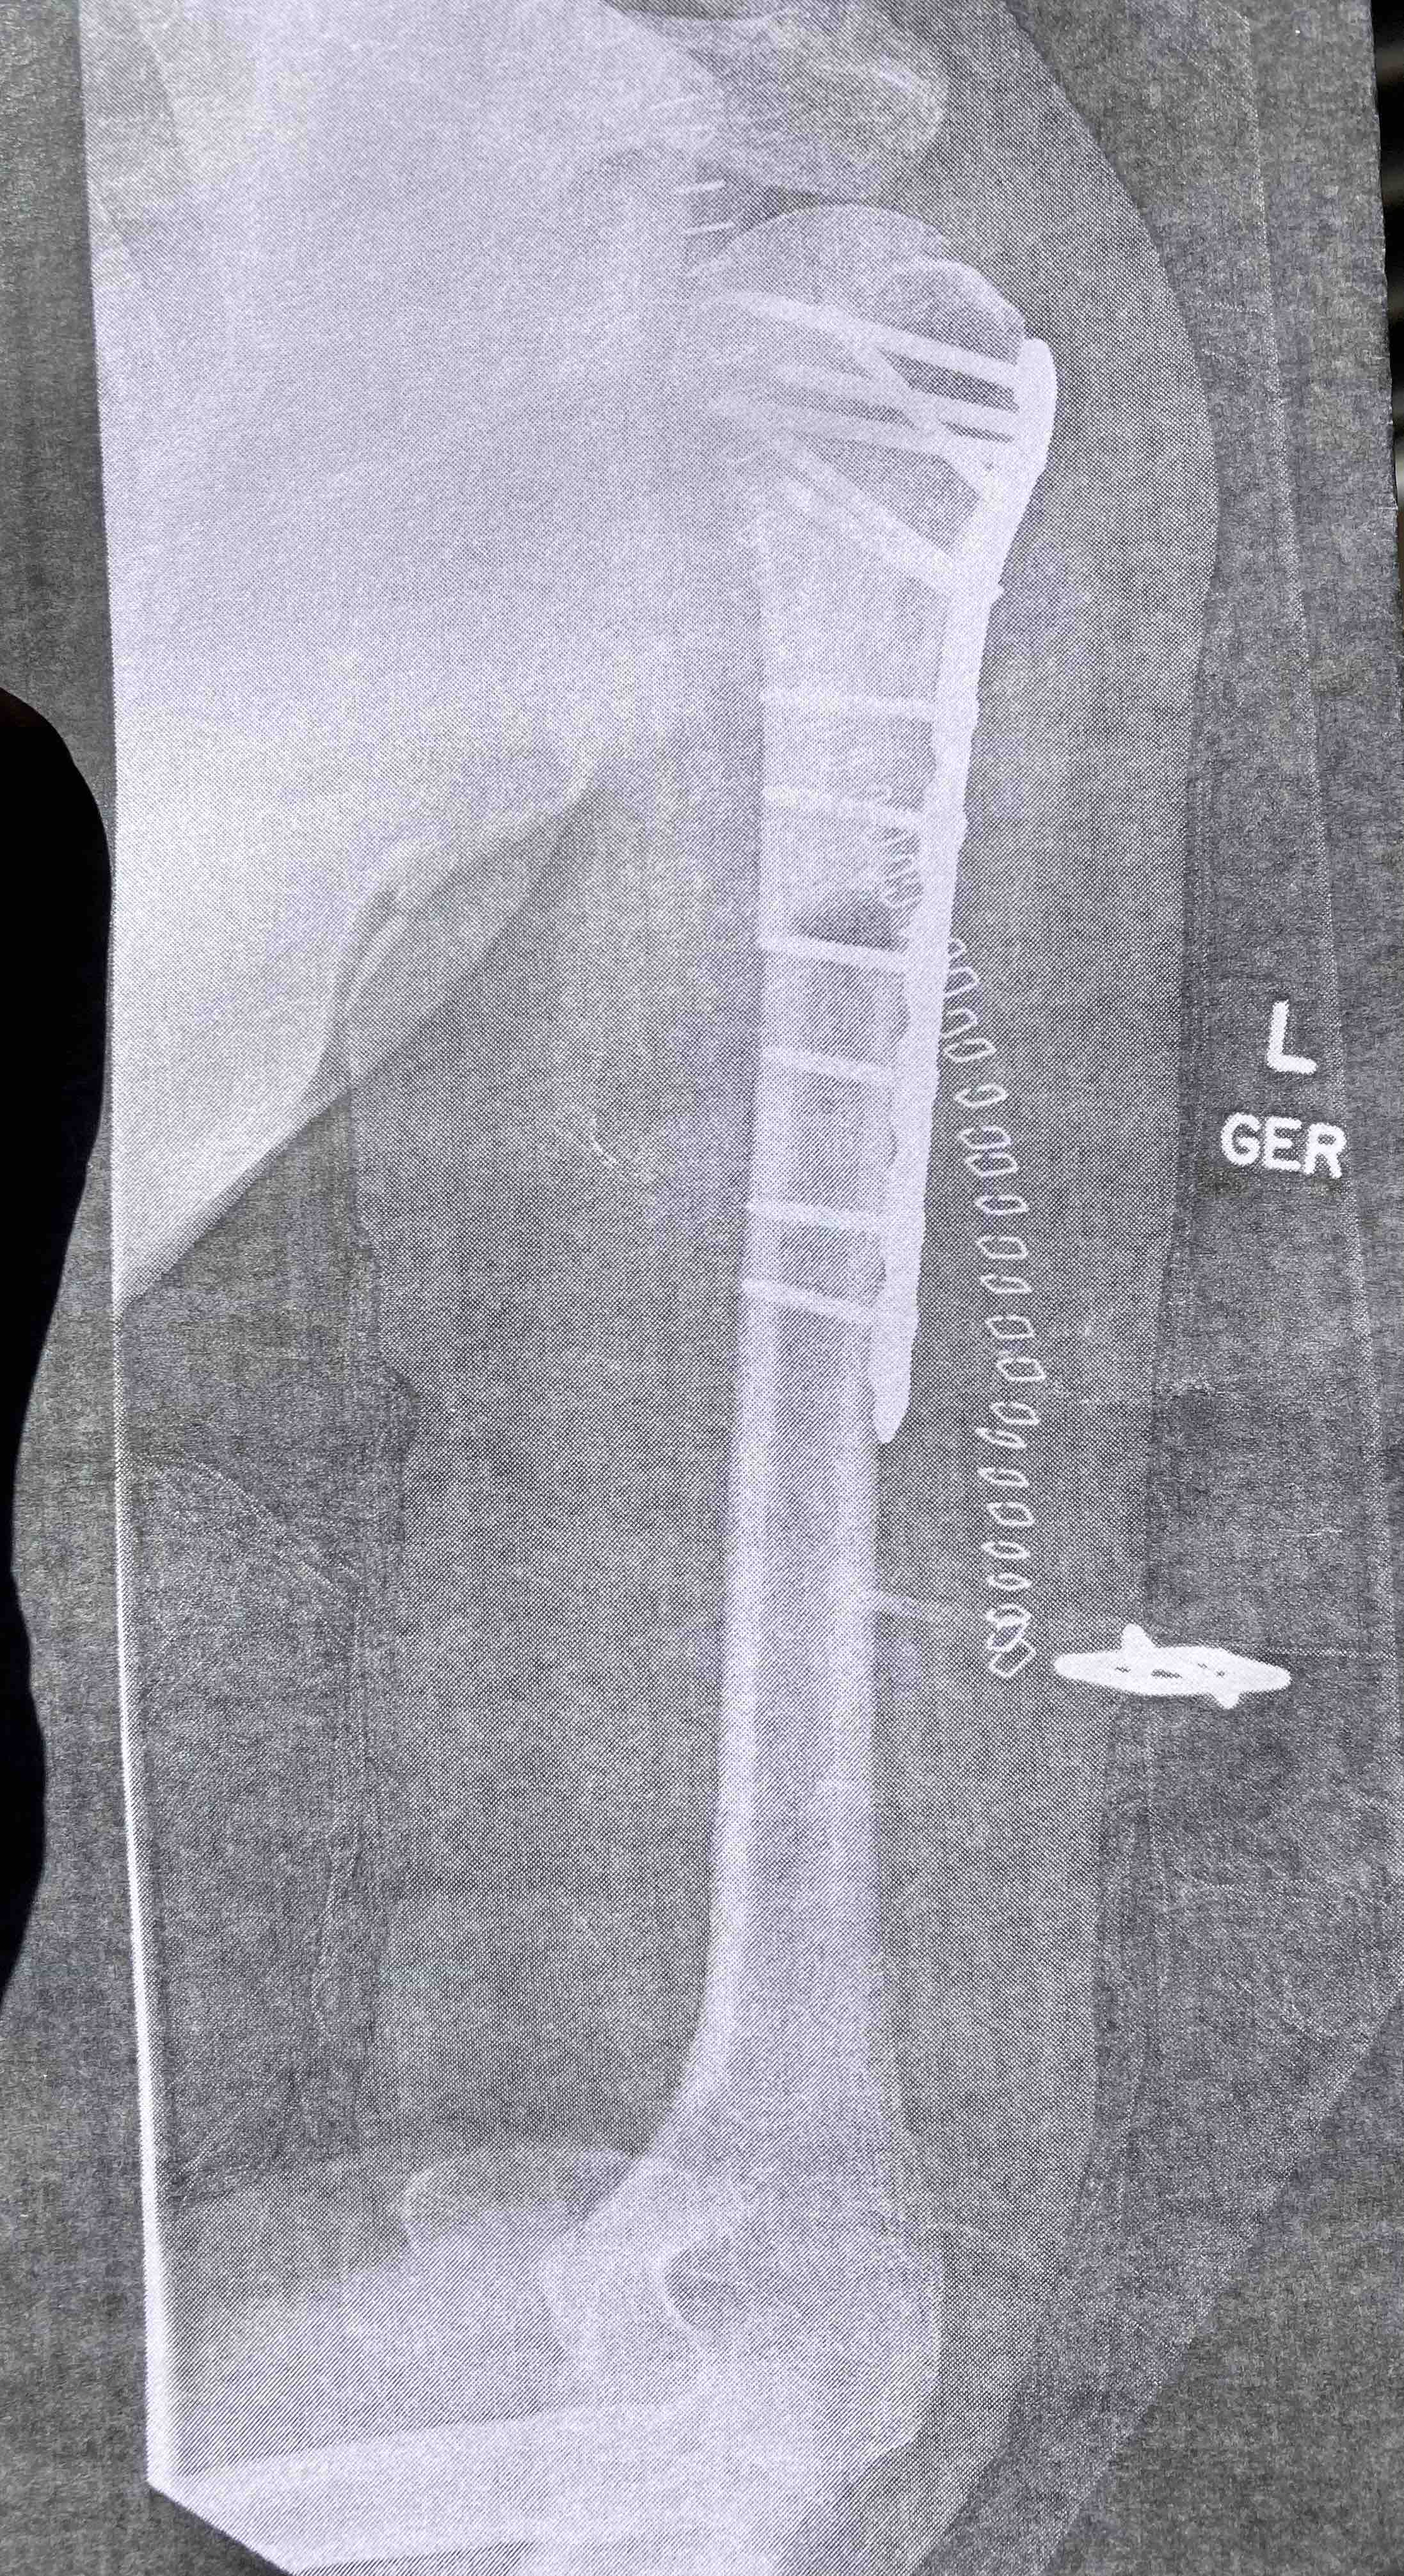

Most of you know that in August of 2022, my husband Donny (only 47 at the time) was diagnosed with stage 4 metastatic renal cell carcinoma (kidney cancer). Since that time, he has endured 3 surgeries, 2 rounds of radiation (with another coming soon), and countless chemotherapy infusions, doctors appointments, and tests including blood work, x-rays, CT scans, and MRIs.